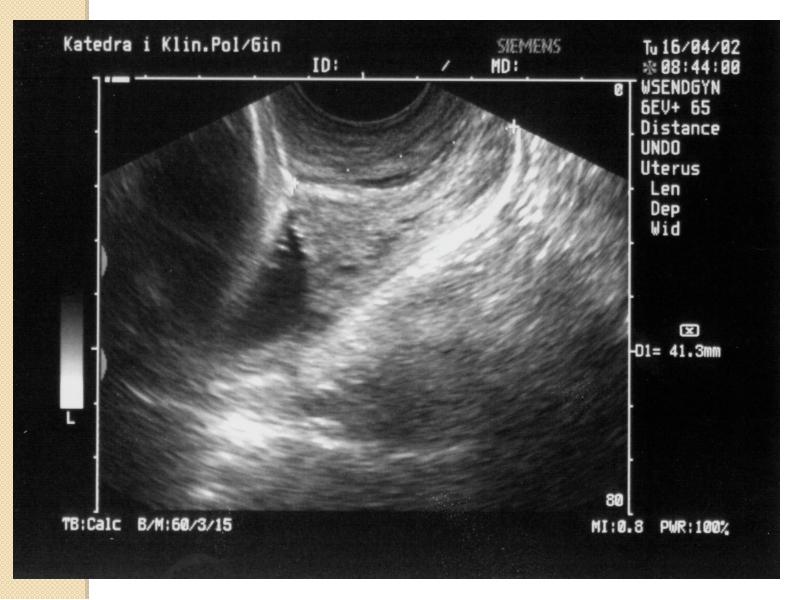

- 45. Niewydolność cieśniowo-szyjkowa Badanie USG Średnia długość szyjki macicy 38-42mm Długość

- 46. Niewydolność cieśniowo-szyjkowa Badanie USG przez powłoki brzuszne: wymaga wypełnienia pęcherza moczowego.

- 47. Niewydolność cieśniowo-szyjkowa Badanie przezpochwowe: pęcherz moczowy musi być opróżniony. należy zidentyfikować